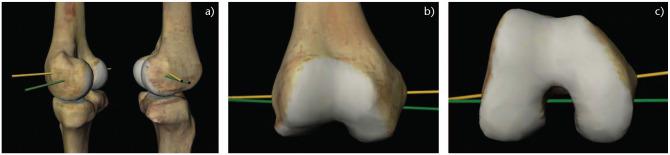

Although mechanical alignment (MA) has traditionally been considered the gold standard, the optimal alignment strategy for total knee arthroplasty (TKA) is still debated.Kinematic alignment (KA) aims to restore native alignment by respecting the three axes of rotation of the knee and thereby producing knee motion more akin to the native knee.Designer surgeon case series and case control studies have demonstrated excellent subjective and objective clinical outcomes as well as survivorship for KA TKA with up to 10 years follow up, but these results have not been reproduced in high-quality randomized clinical trials.Gait analyses have demonstrated differences in parameters such as knee adduction, extension and external rotation moments, the relevance of which needs further evaluation.Objective improvements in soft tissue balance using KA have not been shown to result in improvements in patient-reported outcomes measures.Technologies that permit accurate reproduction of implant positioning and objective measurement of soft tissue balance, such as robotic-assisted TKA and compartmental pressure sensors, may play an important role in improving our understanding of the optimum alignment strategy and implant position. Cite this article: 2020;5:486-497. DOI: 10.1302/2058-5241.5.190093.

尽管机械对线(MA)传统上一直被视为金标准,但全膝关节置换术(TKA)的最佳对线策略仍存在争议。运动学对线(KA)旨在通过尊重膝关节的三个旋转轴来恢复自然对线,从而使膝关节运动更接近自然膝关节。设计外科医生病例系列和病例对照研究表明,在长达10年的随访中,KA TKA具有出色的主观和客观临床结果以及生存率,但这些结果尚未在高质量的随机临床试验中得到重现。步态分析表明,诸如膝关节内收、伸展和外旋力矩等参数存在差异,其相关性需要进一步评估。尚未证明使用KA在软组织平衡方面的客观改善会导致患者报告的结局指标得到改善。能够精确再现植入物定位和客观测量软组织平衡的技术,如机器人辅助TKA和间隔压力传感器,可能在提高我们对最佳对线策略和植入物位置的理解方面发挥重要作用。引用本文:2020;5:486 - 497。DOI:10.1302/2058 - 5241.5.190093。